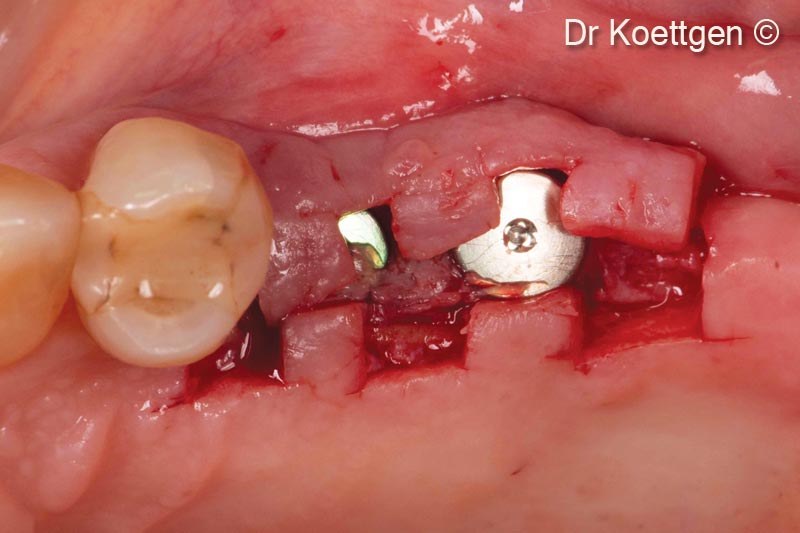

Sau khi nhổ răng, bệnh nhân nữ (63 tuổi) cần tăng cường mô cứng và mô mềm.

Vật liệu sinh học đã qua sử dụng

Apatos®

Lamina®